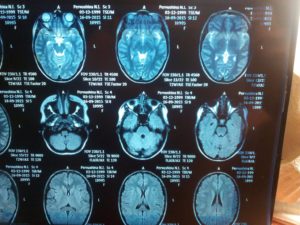

хроническая левосторонняя субдуральная гематома, масс-эффект вправо

Хроническая левосторонняя субдуральная гематома, корональная плоскость

Возможно применение контрастного усиление путем внутривенного введения контраста. Квалифицированный специалист подбирает вид и метод проведения мрт головного мозга до начала исследования.